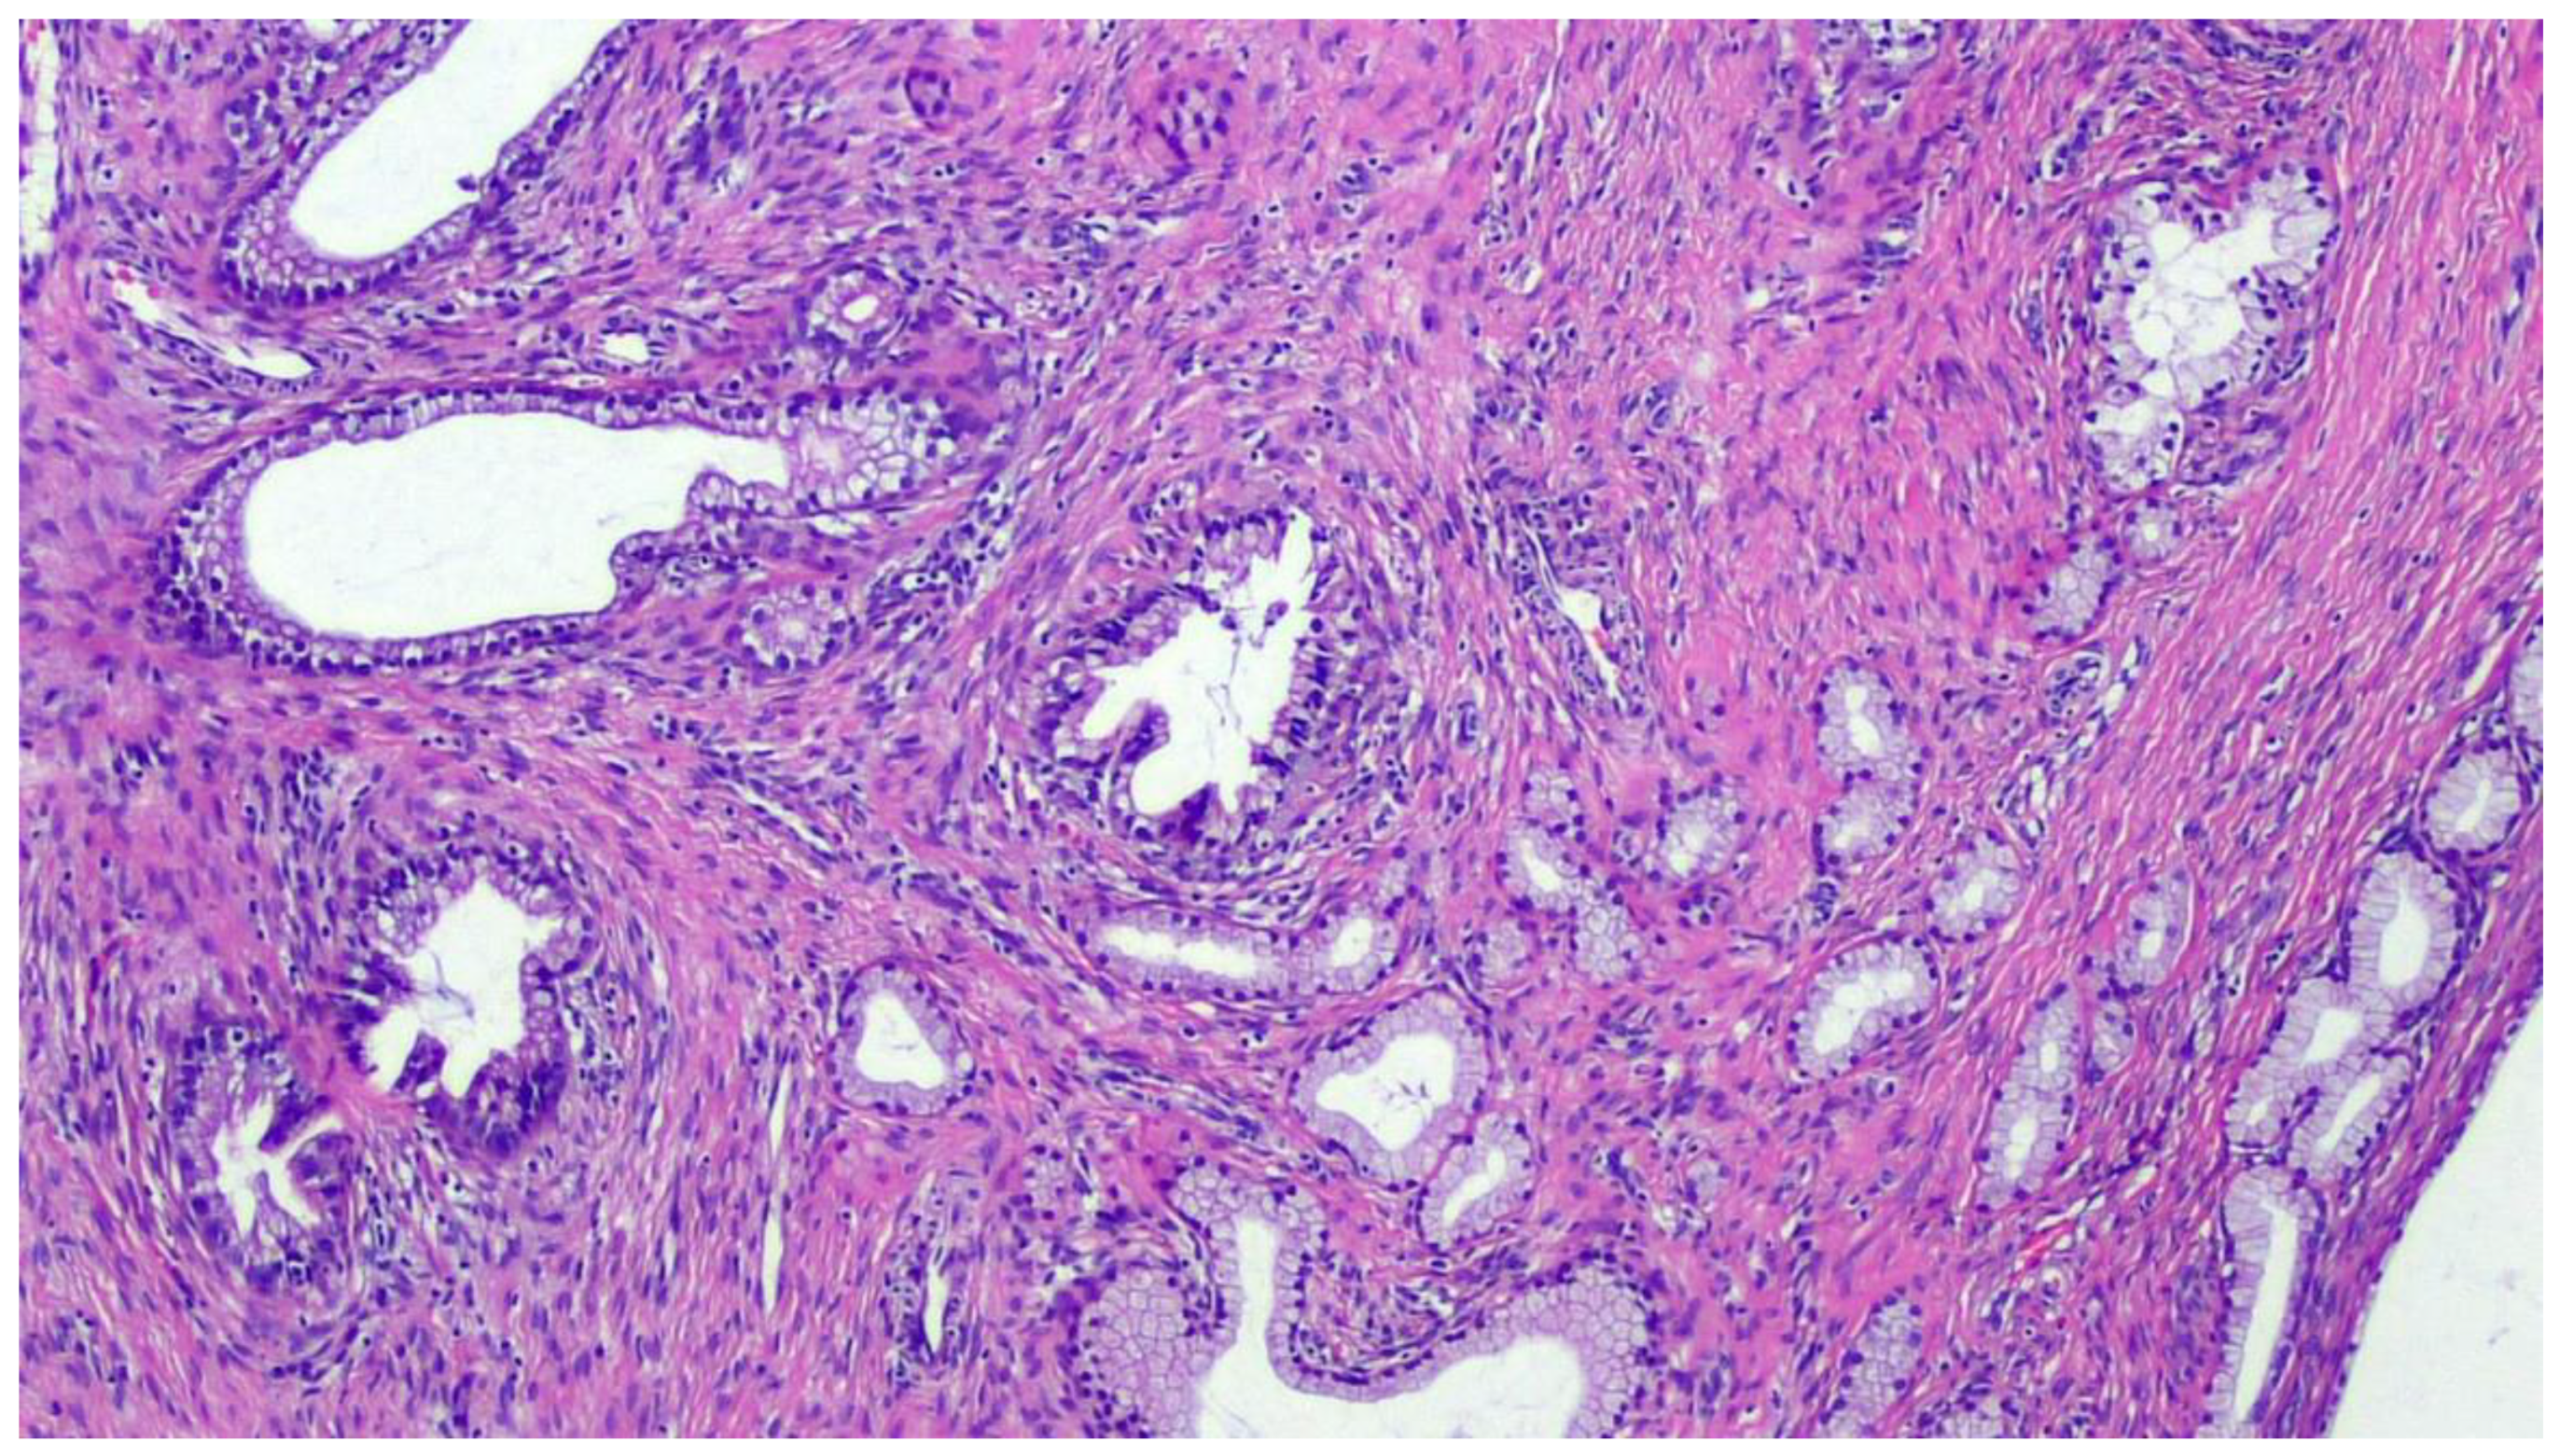

The term “gastric-type” was coined by Japanese research groups who first described this uncommon entity in the 1990s [18]. Of course, it may resemble the gastric and pancreatobiliary epithelial lining (Figure 1).

Over the past two decades, this entity has included a spectrum of endocervical tumors ranging from well-differentiated forms of gastric-type endocervical ADC, such as minimal deviation adenocarcinoma of mucinous type, the so-called “adenoma malignum”, to the poorly differentiated gastric-type endocervical ADC [19]. The most recent World Health Organization (WHO) classification of Tumors of Female Reproductive Organs classifies gastric-type endocervical adenocarcinoma as a distinct type of adenocarcinoma under the category “mucinous carcinoma” of the uterine cervix, establishing this type of tumor as a distinct entity with specific histological features, immunohistochemistry profile, and clinical behavior unique from the usual type of endocervical adenocarcinoma [20]. Gastric-type ADCs are characterized by tumor cells exhibiting voluminous clear or pale eosinophilic cytoplasm, moderate nuclear atypia, as well as distinct cell borders. The latter may configure areas that are indistinguishable from minimal deviation adenocarcinoma. Similar to minimal deviation adenocarcinoma, gastric-type ADC tumor cells contain acidic mucin and express immunomarkers similar to gastric mucus cells, such as HIK1083, lysozyme, and pepsinogen II [21]. It has been documented that gastric-type endocervical ADC behaves more aggressively than HPV-associated endocervical ADC and often displays a more widespread involvement at the time of presentation [21,22]. Strikingly, p16 is usually negative or focally positive, although up to 8–9% of cases have diffuse, strong expression typical of HPV-associated tumors [11,21,23].

Figure 1. Mucinous adenocarcinoma, gastric type. Hematoxylin-Eosin, 10× magnification. This mucinous adenocarcinoma shows gastric-type differentiation. Invasion of the endocervical stroma with variably sized simple cystic glands, some solid areas, and infolded papillae. These tumors are composed of cells with abundant clear or pale eosinophilic cytoplasm and distinct cell borders, displaying enlarged and hyperchromatic nuclei.